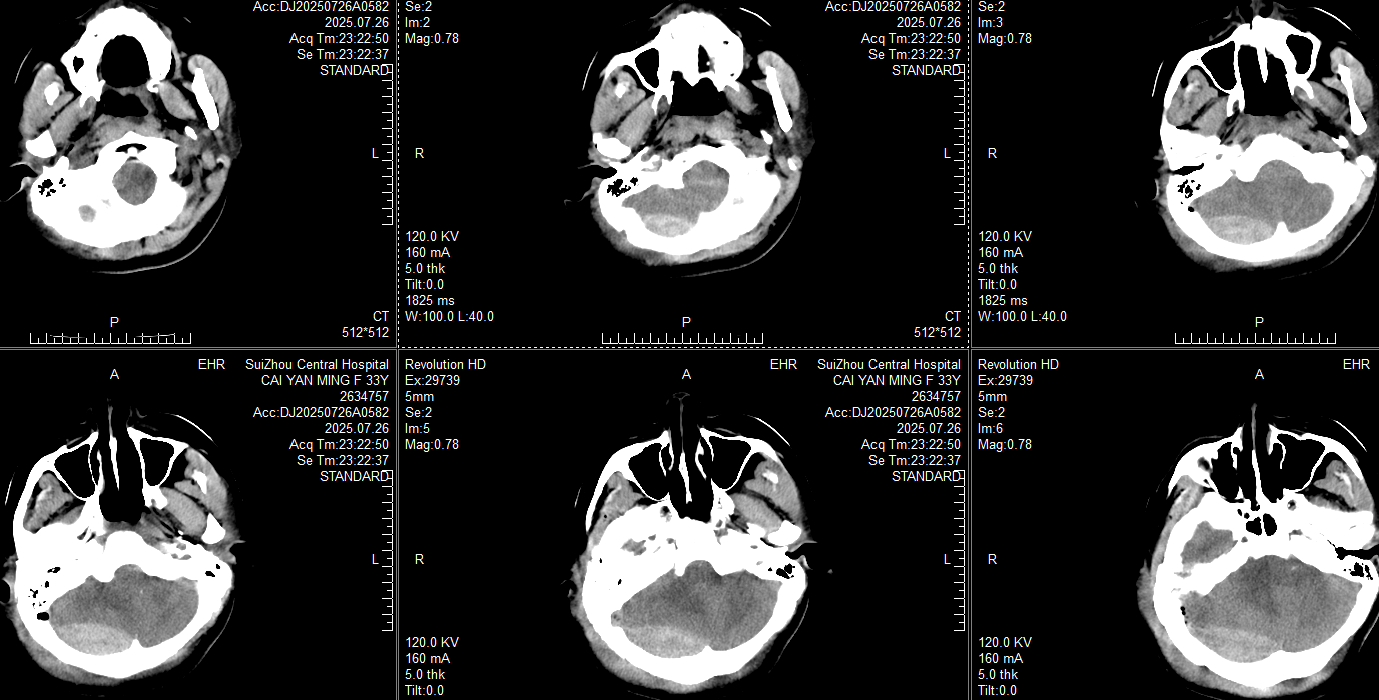

此时患者瞳孔等大同圆直径约2mm,对光反射均存在,颞叶血肿未完全形成,在和家属交代开颅手术方案:右侧枕部开颅清除硬膜外血肿去骨瓣减压,后再复查CT对比右侧颞叶出血进展情况。家属还在考虑手术方案时,23:20患者右侧瞳孔开始放大,立即复查CT: